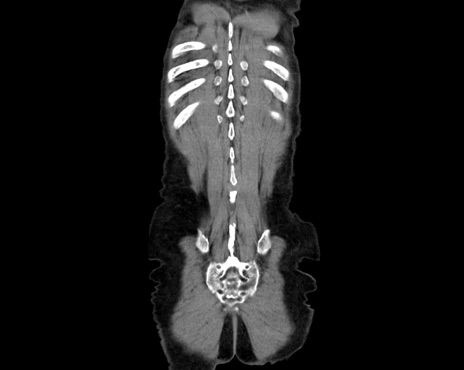

横断像